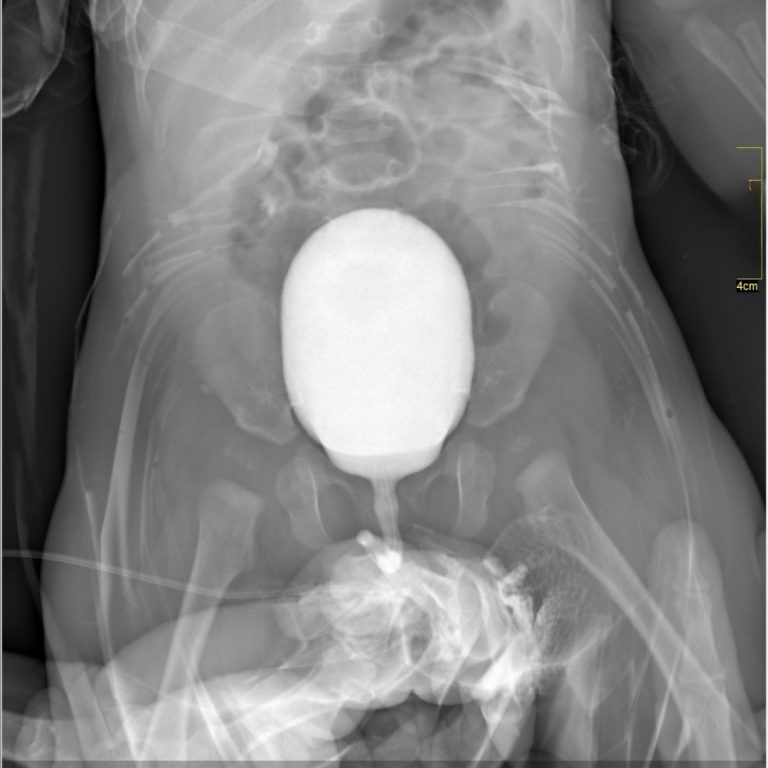

VOİDİNG SİSTOGRAFİ

Voiding Sistoüretrografi (VSUG) mesane ve alt üriner sistemin değerlendirilmesi için kullanılan bir X-ışını ile görüntüleme yöntemi olup mesaneye bir sonda ile verilen kontrast madde aracılığıyla, işeme sırasında idrar yollarının görüntülenmesidir.Çocuklarda üriner sistem infeksiyonunu takiben vezikoüreteral reflü şüphesi varlığında VSUG incelemesine gerek duyulmaktadır.

Voiding sistoüretrografi nasıl yapılır ?

Radyoloji teknisyeni çocuğunuzu inceleme masasına yerleştirdikten sonra çocuğun hareketini engelleyici araçlar kullanabileceği gibi sizden de çocuğu tutma konusunda yardım isteyebilir. Kontrast madde verilmeden önce mesane boşken bir film çekilir. Daha sonra özel bir sıvıyla çocuğunuzun cinsel organını temizlenir ve mikropsuz bir ortam sağladıktan sonra ince bir kateter (ince, esnek bir tüp) idrar yolundan geçirerek mesaneye yerleştirilir. Tüpün ucu kontrast madde içeren bir torbaya bağlanarak yerçekiminin etkisiyle mesane tamamen dolana kadar beklenir.

Mesane dolarken mesaneden üst idrar yollarına kaçış olup olmadığına bakılarak çeşitli filmler çekilir. Mesane tamamen dolduğunda sonda çıkartılır ve çocuk idrarını yaparken seri filmler çekilir.İşeme sona erdiğinde mesanede idrar kalıp kalmadığını görebilmek için bir film daha çekilerek işlem sonlandırılır. İşlem ağrısız olmakla beraber küçük çocuklar hareketleri engellendiğinde ağlayabilmektedirler. Kateter takılmadan önce çocuğunuzun cinsel bölgesi mikroplardan arındırmak için özel bir sıvıyla temizlenir. Bu sıvı soğukluk hissi oluşturabilir. Kateterin takılması ve mesanenin kontrast madde ile doldurulması ağrısız olmakla beraber bazı çocuklar rahatsızlık hissedebilirler. Çocuğunuzun korkmaması ve sakinleşmesi için, radyasyona maruz kalabileceğinizden kurşun önlük giyme şartı ile çekim süresince yanında kalabilirsiniz. Tüm işlemler, yaklaşık 15 dakikada tamamlanır.